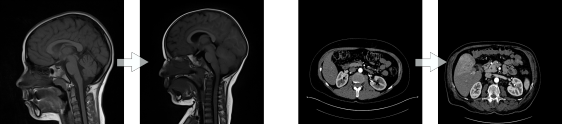

Normalisation of medical images is a important step for data acquisition

Before

linear registration :

After

Non Linear registration